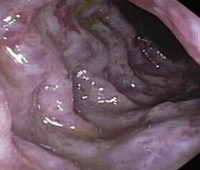

При колоноскопии на ранних стадиях ишемического колита слизистая оболочка отечна, легко кровоточит, со сливными геморрагиями. Могут быть видны синюшные буллезные выпячивания, создающие рентгенологическую картину наподобие «отпечатка большого пальца». В более выраженной стадии обнаруживают неправильной формы язвы, окруженные геморрагически измененной слизистой оболочкой. В последующем возможна трансформация язв в псевдополипы.